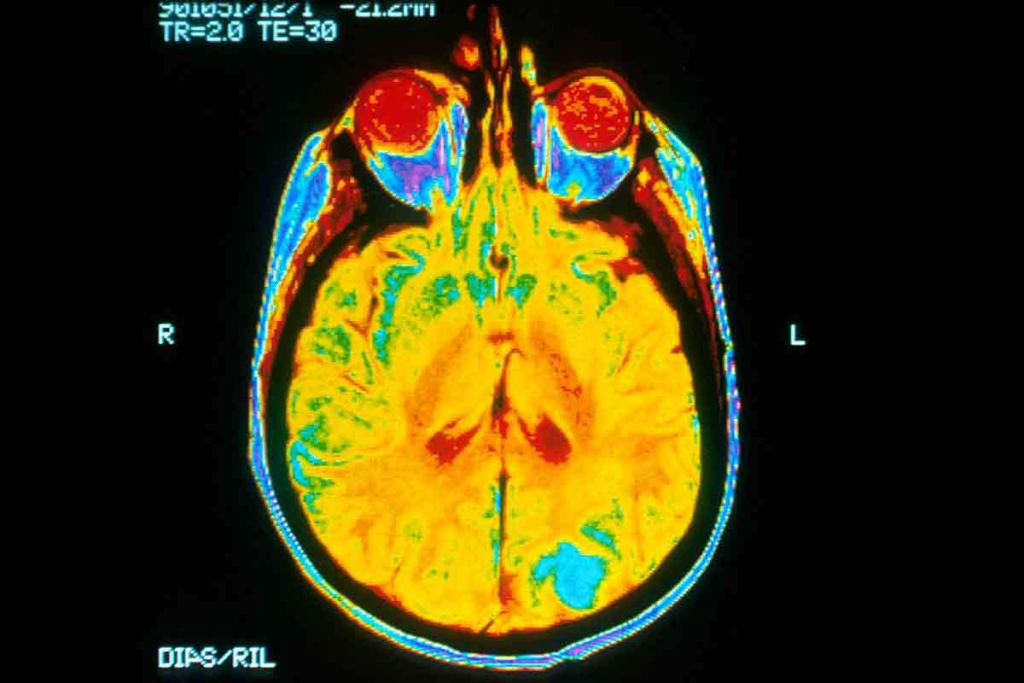

Modern brain imaging is giving us new insights into tumors. It’s changing how we treat brain cancers. MRI and other scans are key in finding and diagnosing tumors.

For a long time, doctors have used CT scans and MRI to look at brain tumors. These methods help find out what the tumor is like and where it is. They are key in diagnosing brain tumors.

Standard MRI scans are used a lot because they can spot soft tissue problems well. They give clear pictures of the tumor’s shape and size. This helps doctors see how big the tumor is and how close it is to important brain parts. Advanced MRI methods like diffusion-weighted and perfusion-weighted imaging give more details about the tumor.